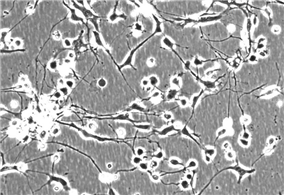

HA;人星形胶质细胞(原代细胞)

HOPC-os;人少突胶质前体细胞-悬浮(原代)

HOPC;人少突胶质前体细胞-贴壁(原代)

HCGC;人小脑颗粒细胞(原代细胞)

HN;人神经细胞(原代细胞)

HMC;人脑膜细胞(原代细胞)

HCPF;人脉络丛成纤维细胞(原代细胞)

HCPEpiC;人脉络丛上皮细胞(原代细胞)

HBVP;人脑血管周细胞(原代细胞)

共 102 条记录,当前 11 / 12 页